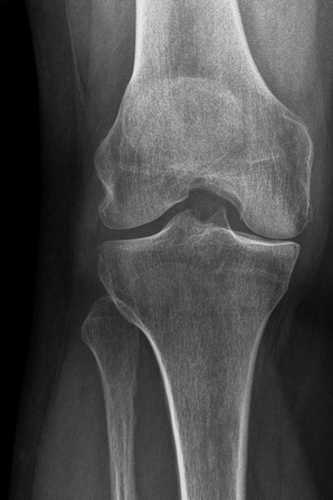

Durch entzündliche Veränderungen der Kniegelenkkapsel und durch Störung der abführenden Blutgefäße können Schmerzen in Ruhe oder auch in der Nacht auftreten. Im Röntgenbild ist der innere oder äußere Gelenkspalt stark verschmälert oder gänzlich aufgehoben.

Knie Röntgen vor OP

Varusgonarthrose Grad 4